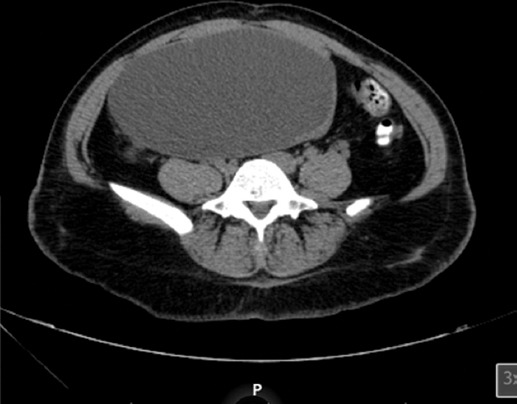

Mujer de 35 años, con hipotiroidismo diagnosticado hace 8 años en tratamiento con levotiroxina, adenoma pituitario diagnosticado hace 8 años en tratamiento con cabergolina durante 5 años, alérgica al medio de contraste y a la indometacina. Inicia su padecimiento actual hace 3 años durante el embarazo con diagnóstico de quiste en anexo derecho. Hace 4 meses comienza con urgencia urinaria, dolor abdominal y sensación de masa abdominal. Exploración física: Glasgow 15, abdomen distendido, peristaltismo normal, presencia de masa abdominal en el flanco derecho, bien definida, dolorosa a la palpación. Laboratorios: leucocitos 7 k/ul (miles por litro cúbico), hemoglobina 14 g/dl, plaquetas 328.0 k/ul (miles por litro cúbico), creatinina 0.6 mg/dl, sodio 140 mmol/l, potasio 3.9 mmol/l, examen de orina no patológico. La TC simple (Figs. 1 y 2) reporta lesión hipodensa, septos delgados ocupando la cavidad pélvica y abdominal, depende de la fijación correcta en relación con el cistoadenoma seroso, comprime la vejiga y desplaza las estructuras adyacentes.

Figura 1 Tomografía computarizada de abdomen y pelvis que muestra un quiste grande (10 × 14 cm) que ocupa la cavidad abdominal.

Figura 2 Tomografía computarizada de abdomen y pelvis que muestra una masa quística de contornos definidos y paredes delgadas.